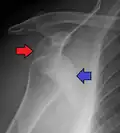

Lightbulb sign indicative of posterior shoulder dislocation shown on the left. On the right, the same shoulder after reduction.

Posterior dislocations are uncommon, and are typically due to the muscle contraction from electric shock or seizure.[6] They may be caused by strength imbalance of the rotator cuff muscles. People with dislocated shoulders typically present holding their arm internally rotated and adducted, and exhibiting flattening of the anterior shoulder with a prominent coracoid process.

Posterior dislocations may go unrecognized, especially in an elderly person[15] and in people who are in the state of unconscious trauma.[16] An average interval of 1 year was noted between injury and diagnosis in a series of 40 people.[17]